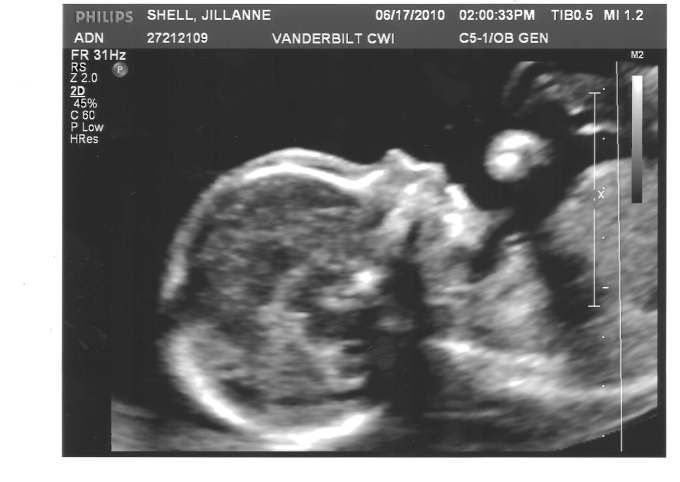

Most importantly, Baby Jack is healthy, thank God!